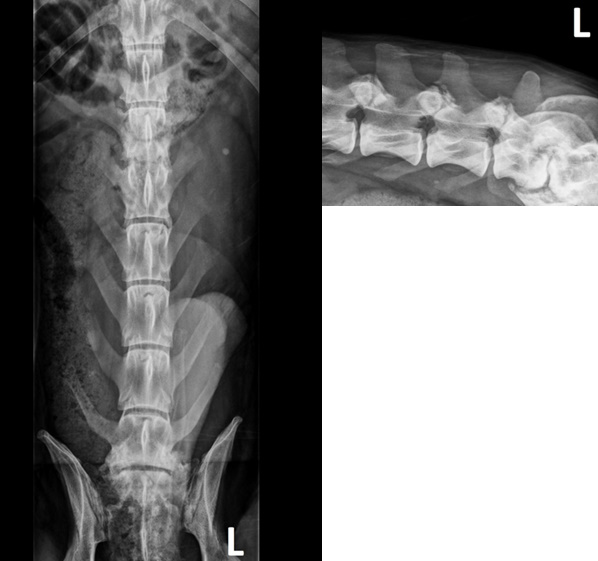

Η διάγνωση βασίζεται συνήθως στην κλινική υποψία και στην απεικονιστική διερεύνηση. Οι απλές ακτινογραφίες συχνά αποκαλύπτουν στένωση του μεσοσπονδύλιου διαστήματος, λύση των παρακείμενων τελικών πλακών και ποικίλου βαθμού σκλήρυνση. Στο 40% των περιπτώσεων εμπλέκονται πολλαπλά μεσοσπονδύλια διαστήματα συνεπώς συνιστάται ακτινογραφικός έλεγχος ολόκληρης της σπονδυλικής στήλης. Οι ακτινογραφικές αλλοιώσεις μπορεί να μην είναι εμφανείς έως και 2–4 εβδομάδες μετά την έναρξη των κλινικών συμπτωμάτων.

| Πλάγια ακτινογραφία σπονδυλικής στήλης με αλλοιώσεις δισκοσπονδυλίτιδας σε πολλά μεσοσπονδύλια διαστήματα. |

Ορθογώνιες προβολές της οσφυϊκής μοίρας της σπονδυλικής στήλης. Στην κοιλιοραχιαία προβολή απεικονίζεται έντονη παραμόρφωση της οπίσθιας τελικής πλάκας του Ο2 και της πρόσθιας τελικής πλάκας του Ο3, με στένωση του μεσοσπονδύλιου διαστήματος Ο2–Ο3 και μέτρια παραμορφωτική σπονδύλωση στο επίπεδο αυτό. Στην πλάγια προβολή απεικονίζεται διεύρυνση των αρθρικών αποφύσεων της οσφυϊκής μοίρας με ανώμαλο περιαρθρικό σχηματισμό νέου οστού. Απεικονίζεται στένωση του μεσοσπονδύλιου διαστήματος Ο7–Ι1 με σκλήρυνση των παρακείμενων τελικών πλακών και παραμορφωτική σπονδύλωση στο επίπεδο αυτό.